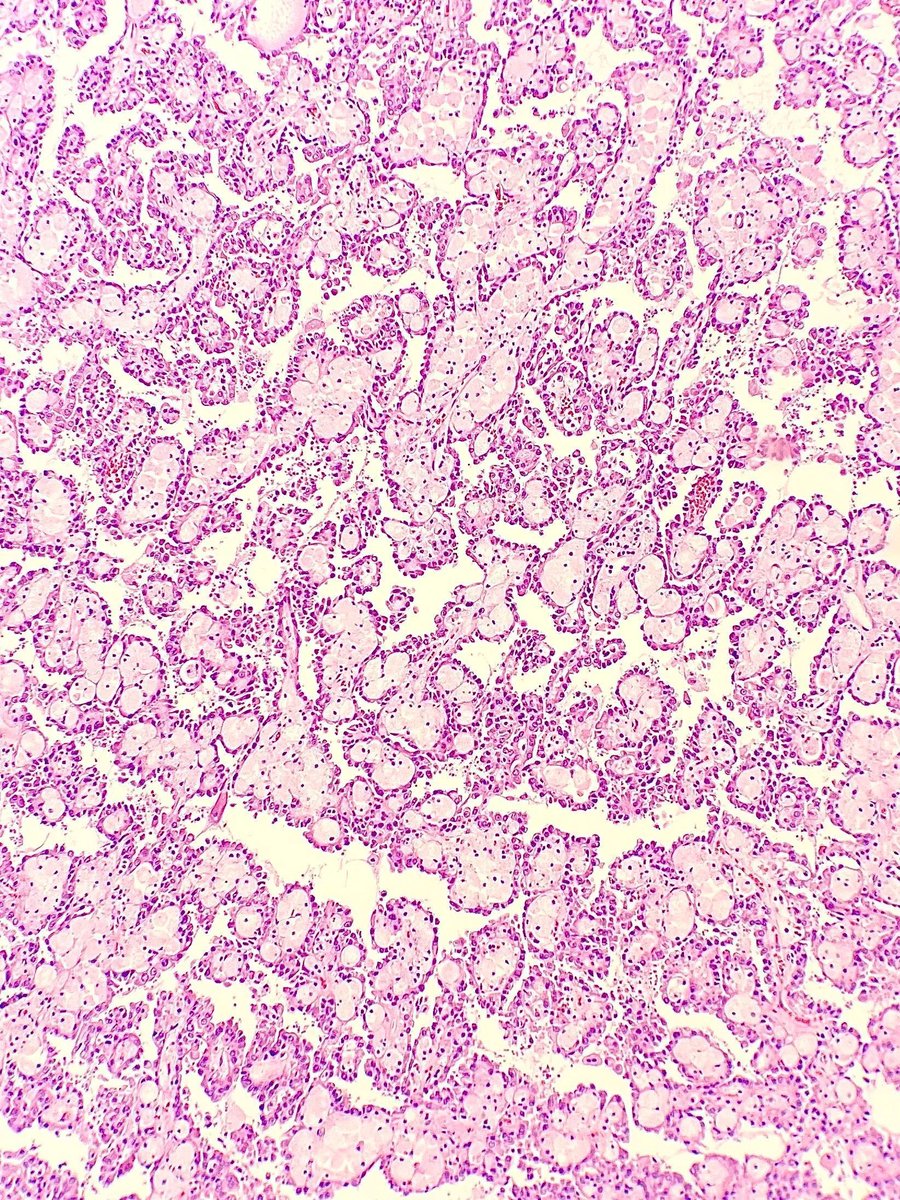

@megha_lalcheta

Dr. Megha Lalcheta MD

3 days

H&E Bouquet 💐 #Pathart A case of renal lymphoma ( showing glomeruli and sheets of malignant lymphoid cells) #Pathology #Renalpath #pathresidents #Renallymphoma #Surgpath #PathX #PathTwitter

0

10

38